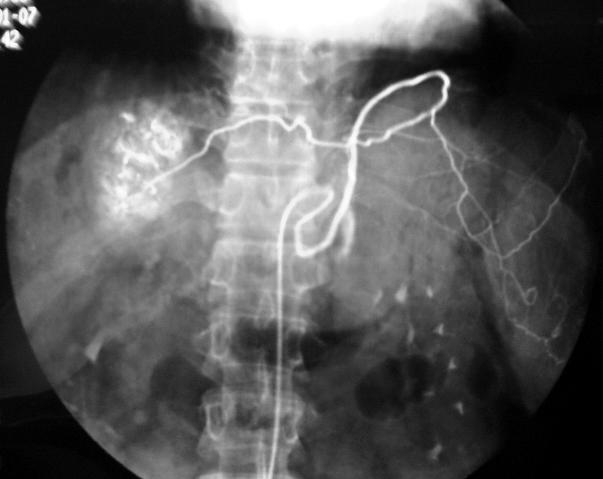

透过体表,导管是到达了病变血管一目了然

第三,导管等介入器材能够从生理腔道(此类操作可达到无创的目标)或血管内自由行进,从来就不会“迷路”,因而能够从对病人伤害最小也最方便的部位进入,实现“远道施术、管针远达”,避免伤及重要器官,避免华佗“头痛医头”一定要开颅而被曹操猜疑处死的悲剧。